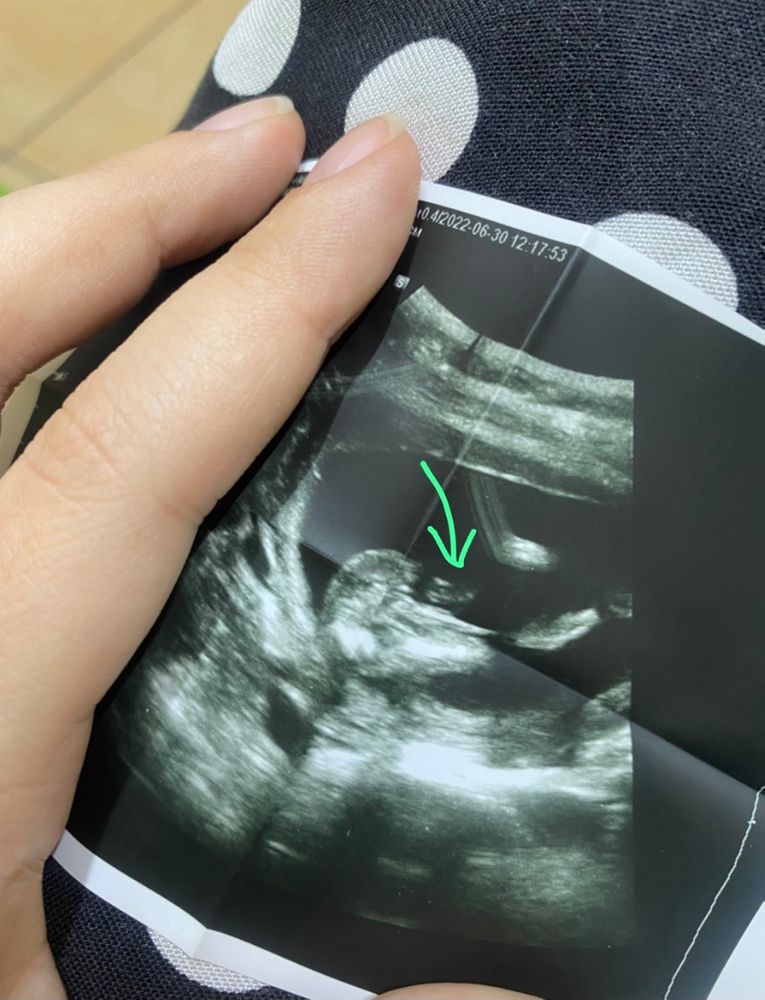

Мальчик или девочка ?

Mama Sveta, Изображение Вот стрелочкой навела на самое интересное

Элина, если мне зрение не изменяет😁 то я отчётливо вижу женские гениталии , две белые полосочки это и есть ПГ девочки , я уже третью жду, и УЗИ прошла вдоль и поперек, оставлю 5% на мальчика, а 95 девочка

девочка похоже,полосочки )) то что там торчит пуповина наверное

Счастье есть , узист говорит вроде бы на девочку похоже, но тоже сомневается

Вижу девочку, а сверху возможно просто пуповина

Девочка 🌸🌸🌸